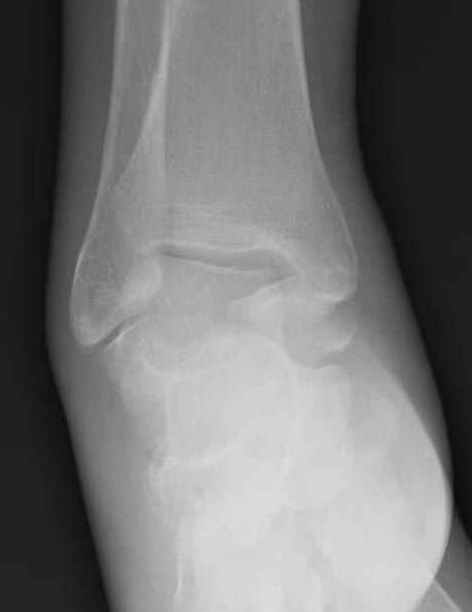

Уважаемые участники русского Ортофорума, поздравляю всех со всеми прошедшими праздниками: Новым годом, Рождеством, Hanukkah, Kwanzaa, желаю участникам всего наилучшего и здоровья.Повреждение таранной кости.Больной 81г автоавария, повреждение таранной кости, здесь снимки. Какие рекомендации?Djoldas Kuldjanov, MDDepartment of Orthopedic SurgerySt. Louis University Medical Center

Вообще то мало данных: торчит ли осколок под кожей, сопутствующая паталогия (атеросклероз, диабет), сколько времени прошло после травмы? Я думаю, что в данном случае можно ограничиться или небольшим вмешательством вплоть до удаления дистального отломка из небольшого разреза, или наложением аппарата с дистракцией переднего отдела стопы в эквинусе, может быть удастся этот отломок и вправить. Опорная функция в любом случае должна сохраниться при любом варианте лечения, не думаю что будет страдать кровоснабжение таранной кости. Я когда то удалил дистальную половину таранной кости, с последующим анкилозированием в тарано-ладьевидном суставе, хотя более опытные товарищи советовали провести астрагалэктомию, но тем не менее тогда результат оказался хороший. Конечно объязательно назначение препаратов улучшающих микроциркуляцию, противоотечная терапия и т.п. Удачи.

Вдогонку по поводу перелома таранной кости, больная 81, не страдает диабетом, перелом закрытый, в первый же день поступления ограничились временным наружным фиксатором (как на снимке).

Планировалась открытая фиксация после спадения отека, но больная пожелала лечиться по месту жительству в другом штате..